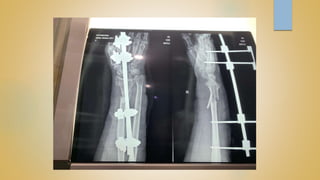

 OPERATIVE

CLOSED REDUCTION AND PERCUTANEOUS K-WIRING

OPEN REDUCTION AND INTERNAL FIXATION

EXTERNAL FIXATOR APPLICATION